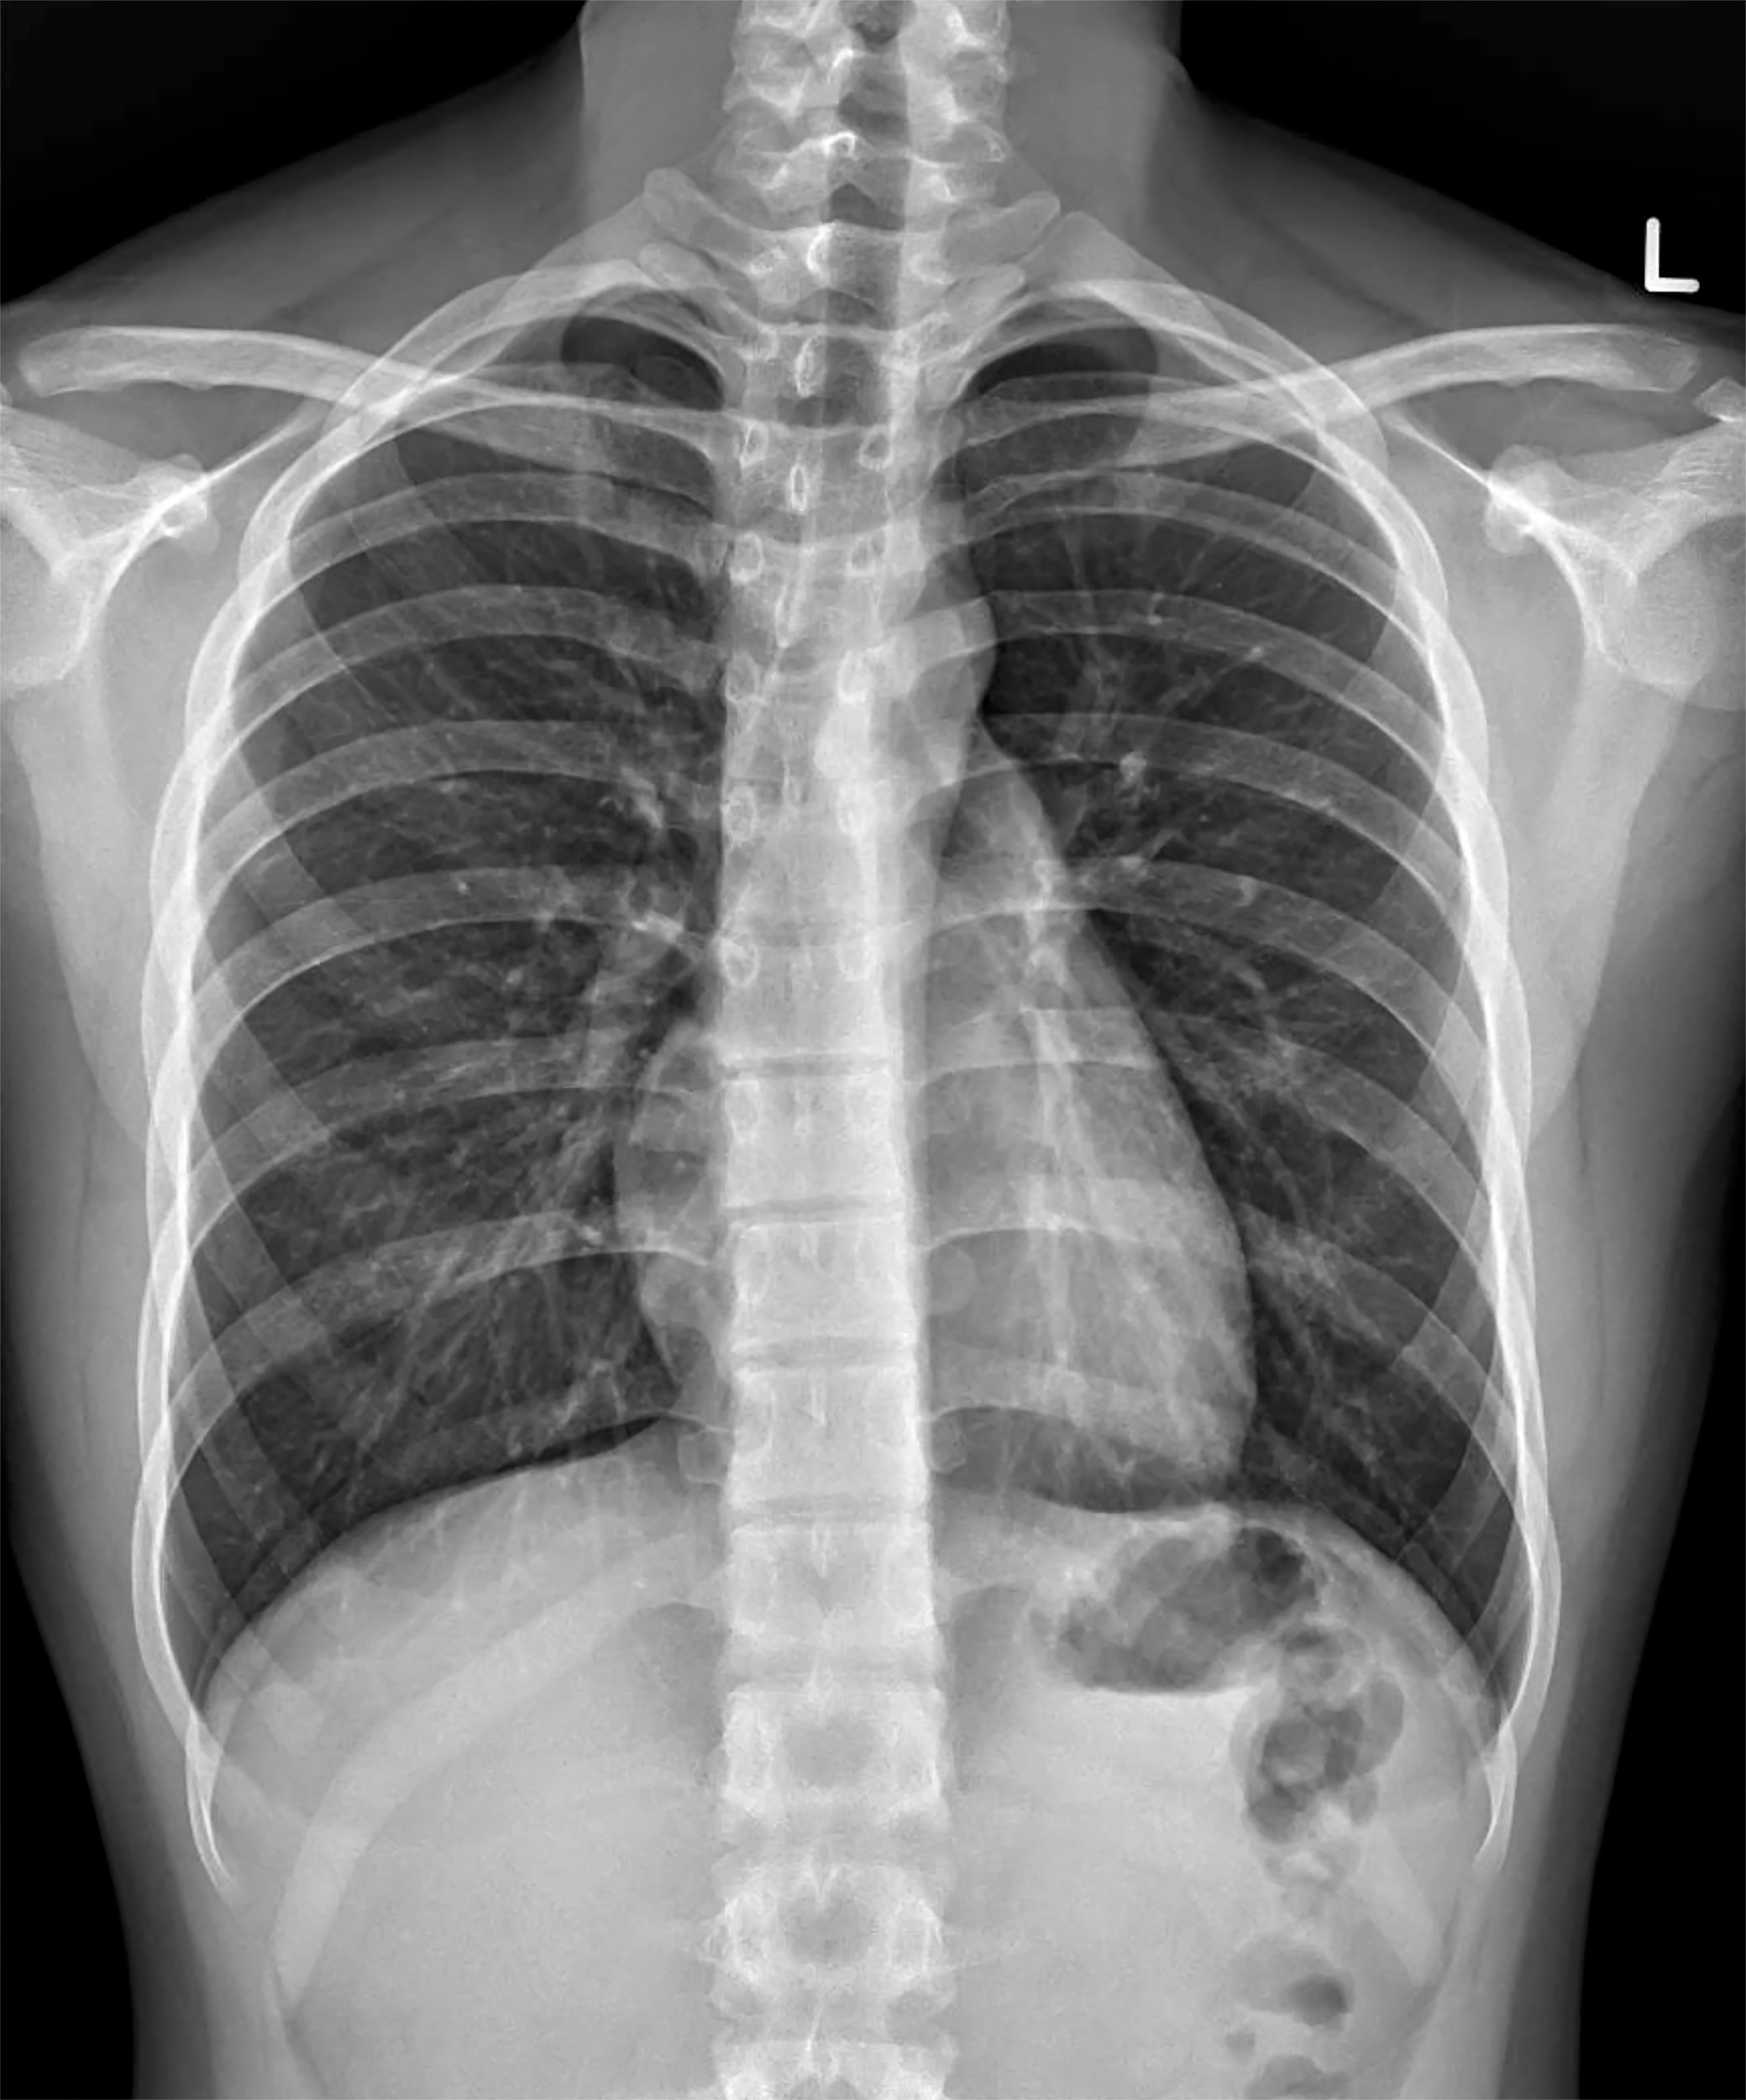

Meanwhile, deep-learning models applied to chest x-rays obtained for other clinical reasons have shown promise in opportunistic osteoporosis screening, particularly among middle-to-older-aged individuals, they added.

Their scenario considered the cost-effectiveness of opportunistic screening using chest x-rays analyzed with deep learning, followed by treatment, compared with a scenario with no screening and treatment. Based on five million individual simulations, the model estimated total healthcare costs, fractures, life years, and quality-adjusted life years (QALYs) for both scenarios.